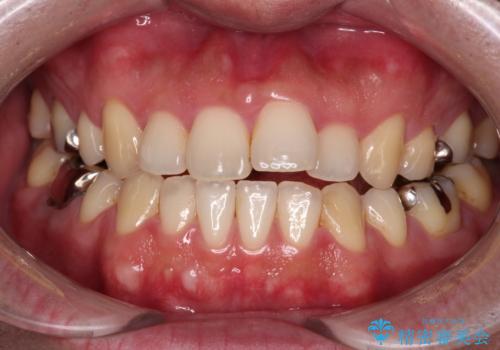

- 抜歯矯正の後戻りを気にして来院された患者様です。

舌の突出癖によるオープンバイトになり、前歯の叢生が後戻りしていました。

舌のトレーニングを行いながら、インビザラインを用いて矯正治療を行うこととしました。